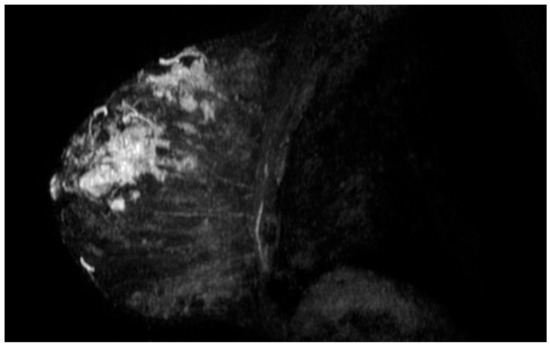

| Breast invasive ductal carcinoma | amplification | amplification | amplification | negative | negative | P191fs*18 | |